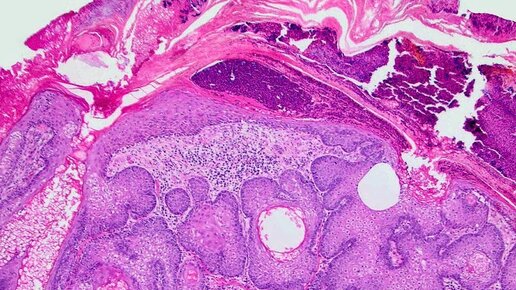

Пищеварительная система – это сложный комплекс органов, отвечающий за переработку пищи, извлечение из нее необходимых питательных веществ и удаление непереваренных остатков. Нарушения в работе этой системы могут приводить к серьезным проблемам со здоровьем. Пищеварение – это многоступенчатый процесс, включающий в себя механическую и химическую обработку пищи. Ротовая полость Глотка и пищевод - пища проглатывается и перемещается по пищеводу в желудок благодаря перистальтическим сокращениям мышц. Желудок Тонкий кишечник - основной этап переваривания и всасывания питательных веществ...